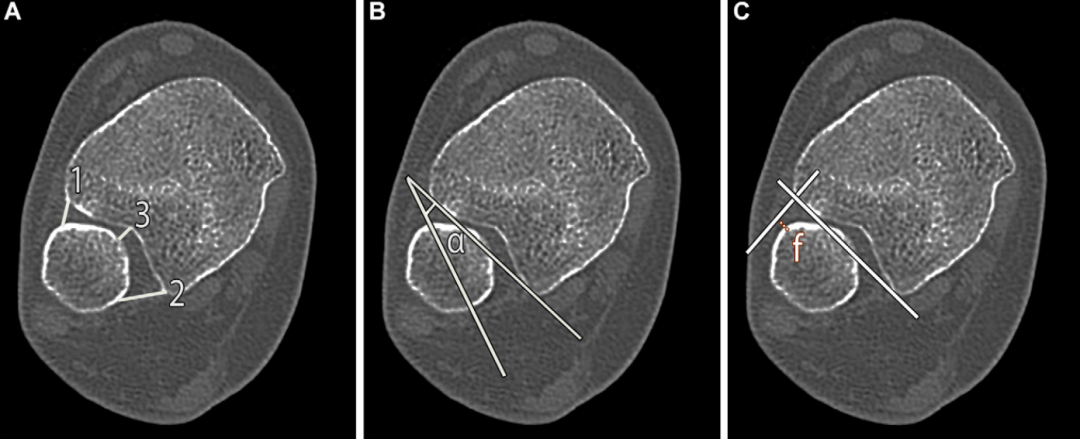

与常规X线摄影相比,CT评估胫腓联合增宽的准确性更高,是评估可疑不稳患者、检出隐匿性骨折的重要辅助手段。对可疑胫腓联合损伤的CT检查方案,需在中立位获取双侧踝关节的对比图像,可在足部下方放置丙烯酸支架以保证体位标准化。

与标准X线测量一致,多数CT测量指标均在胫骨远端关节面上方10mm处获取。研究表明,以踝关节面水平胫腓联合最窄处增宽2mm为阈值,诊断胫腓联合分离的敏感性为76%、特异性为81%,较关节镜检查结果更优,且诊断效能优于其他CT 测量指标;但该研究未与健侧进行对比。此外,CT测量的最佳位置和参考值仍存争议,需进一步研究验证该影像学诊断方法的有效性。

关节镜是诊断胫腓联合不稳的金标准,通常将踝关节面水平胫腓联合增宽大于 2mm 定义为关节不稳;但近期一项研究提出,以腓切迹前部增宽2.9mm作为诊断阈值。

在胫骨关节面上方10mm处进行的其他CT测量指标包括:腓骨与胫骨切迹前、后关节面之间的距离、腓骨旋转角,以及腓骨相对于胫骨的移位距离: